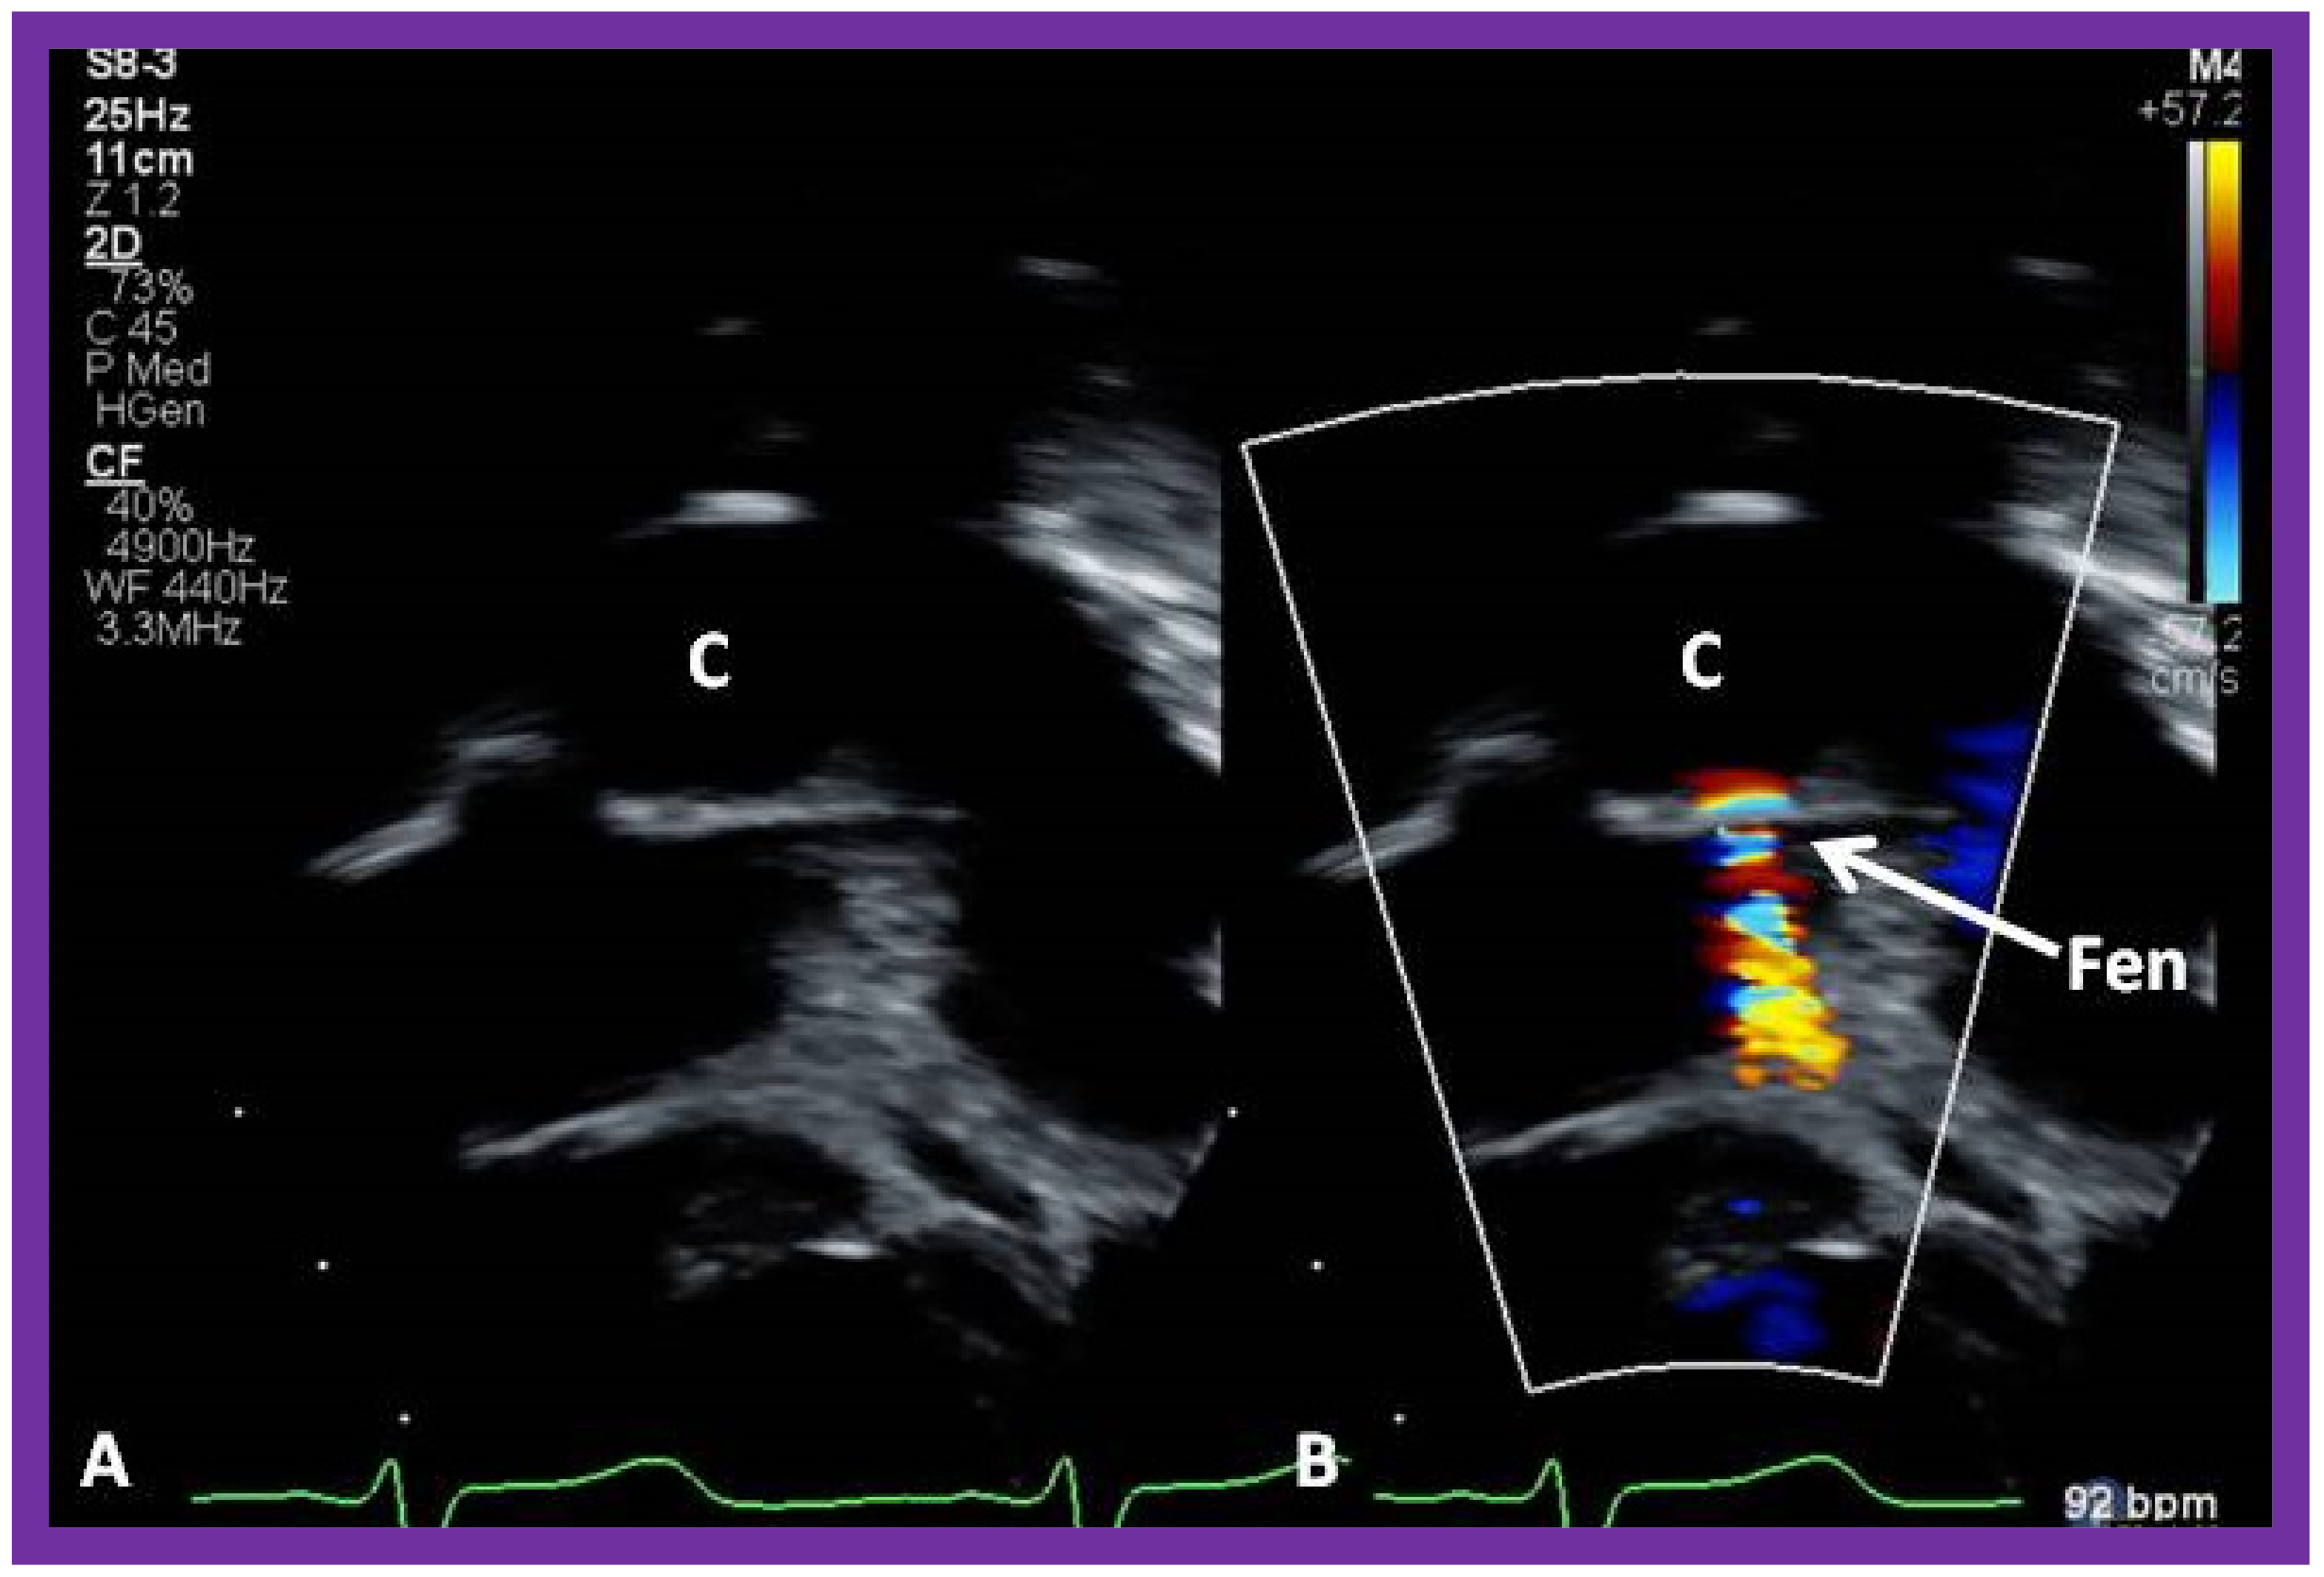

10.4.1. Stage IIIA

10.4.2. Stage IIIB

11. Post-Fontan Follow-Up